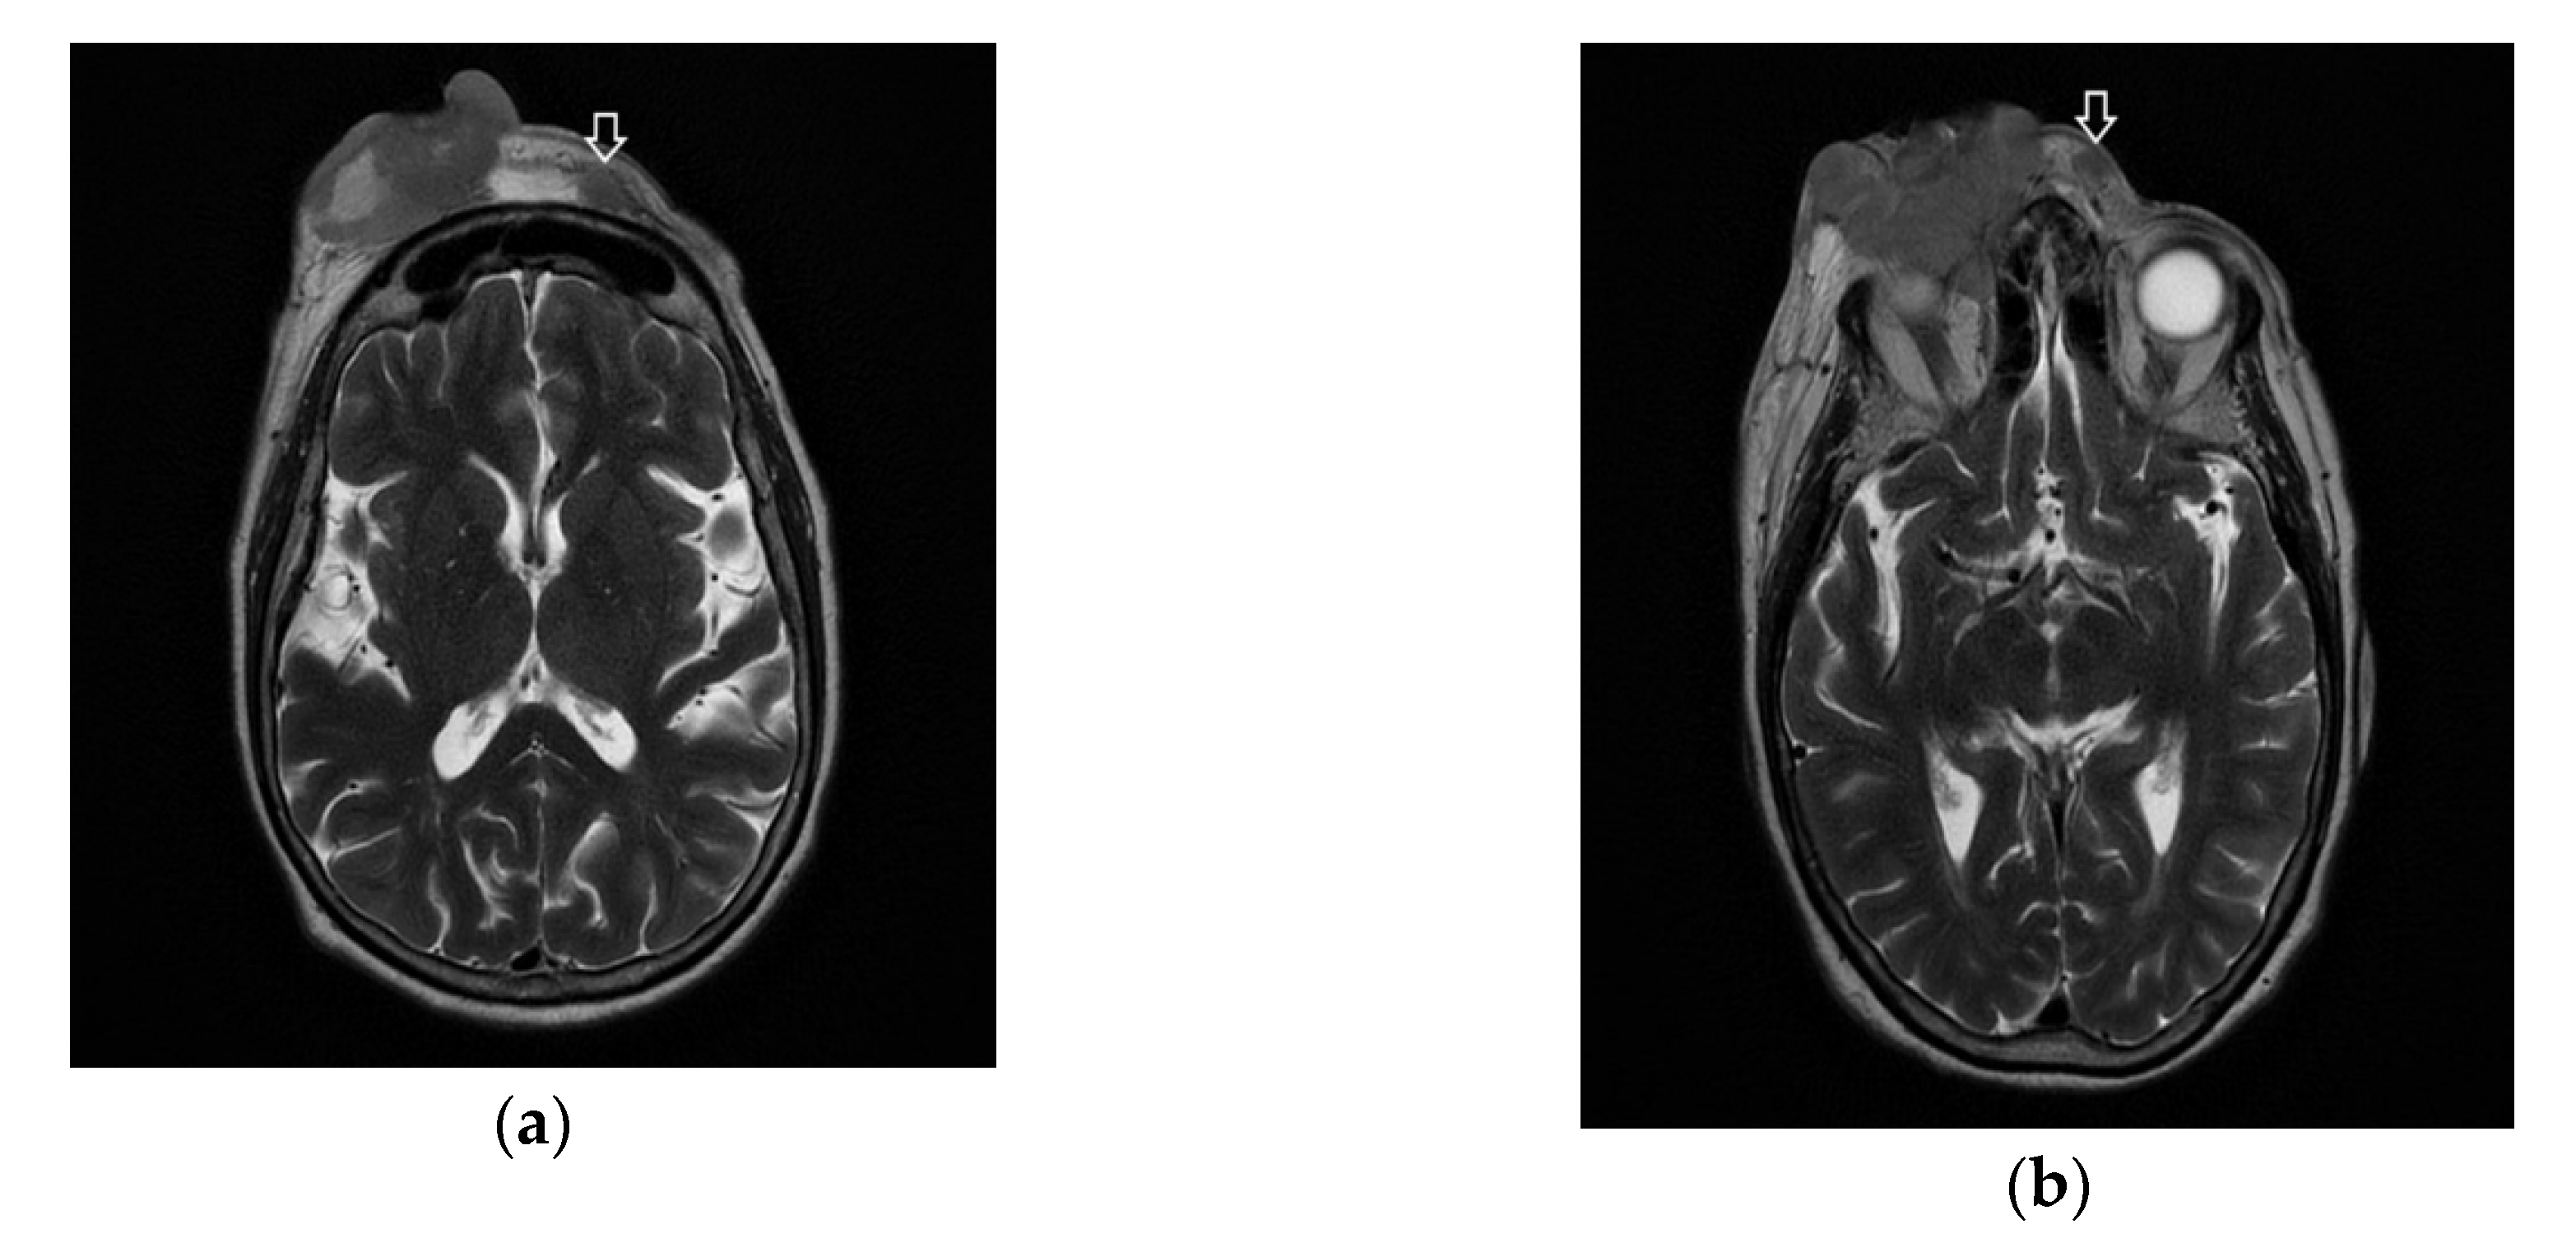

Following the immunohistochemical study, we obtained the following conclusive results. The tumor cells were intensely positive for CD3 (Figure 3b) and CD7 (Figure 3g), a relatively large number of tumor cells were positive for CD2 (Figure 3d) and CD4 (Figure 3e), and only a small population of T lymphocytes or some atypical larger cells were positive for CD8 (Figure 3f), with a CD4+/CD8+ ratio favoring CD4+ cells. Tumor cells were negative for CD30 (Figure 3i), CD5 (Figure 3c), and CD 56 (Figure 3h). A small population of atypical lymphocytes were positive in granzyme B after immunohistochemical staining. The cell proliferation index quantified by immunolabeling for Ki-67 was estimated and quantified at 80–85% (Figure 3j). Following the morphological examination correlated with special stains, the diagnosis of primary cutaneous T-cell lymphoma NOS was established. Whole-body CT was performed and revealed tumor formation in the soft epicranial parts, right frontal area, and supraorbital area, with dimensions of 22/50/45 mm. The lesion affected the upper eyelid and the paranasal region, with no signs of ocular or intracranial invasion. In the frontal on the median and parasagital line on the left, epicranial area, adjacent to the described lesion, another structure with 35/15 mm contrast socket was highlighted. The dynamic contrast-enhanced magnetic resonance imaging (MRI) revealed a large, inhomogeneous lesion, with infiltrative, invasive contour. The origin of the tumor was most probably from the periorbital superficial tissues, with invasion in the orbit and direct contact to the anteromedial aspect of the ocular globe without the presence of a cleavage plane between the two structures (Figure 4a,b and Figure 5a,b). Figure 4a shows that the T1 FSE (fast spin echo) axis and sagittal T1 FSE contrast-enhanced with fat-saturation sequence was not enhanced (a), whereas Figure 4b shows inhomogeneous enhancement of the lesion, with superficial tissue origin and invasion in the right orbit. Figure 5a,b depict the axis T2 PROPELLER sequence showing the necrotic areas in the primary and secondary lesion, satellite lesion in the superficial tissues of the frontal region (marked by arrows in the picture). A restricted diffusion on diffusion weighted imaging (DWI) sequences was observed, with an apparent diffusion coefficient (ADC) value of 0.873 × 10−3 mm2/s on the ADC map (Figure 6a). Dynamic contrast-enhanced MRI (DCE-MRI) imaging showed a type III (C) curve highly suggestive for malignancy (Figure 6b), and a high constant transfer (ktrans) value was observed, pointing to a possible good response to radiochemotherapy (Figure 7). In the proximity of the left frontal area, two nodular superficial lesions were identified, suspected of secondary nodules.

Figure 4. Ax T1 FSE non-enhanced (a) and sagittal T1 FSE contrast-enhanced with fat-saturation sequence (b). Inhomogeneous enhancement of the lesion, with superficial tissue origin and invasion in the right orbit.

Figure 5. (a,b) The ax T2 PROPELLER sequence showing the necrotic areas in the primary lesion and secondary, satellite lesion in the superficial tissues of the frontal region (arrows).